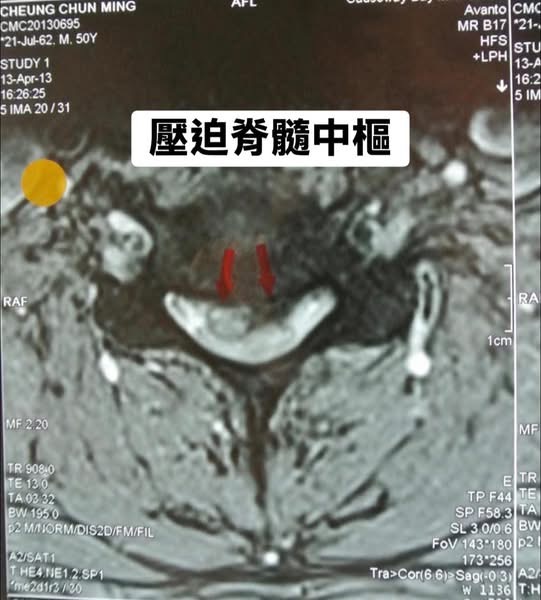

在脊椎醫學的世界裡,精準的影像分析是治療的靈魂。當我將她那張顯示嚴重壓迫的 MRI 影像放大(如圖紅色箭頭處),逐一解釋神經受壓的機轉時,Sofia 眼神中的迷惘轉化成了安心。她終於知道自己的壓迫確實很嚴重,但因為她沒有大小便失禁!手腳很痛但還是有力氣,重點是她肌肉還沒有萎縮